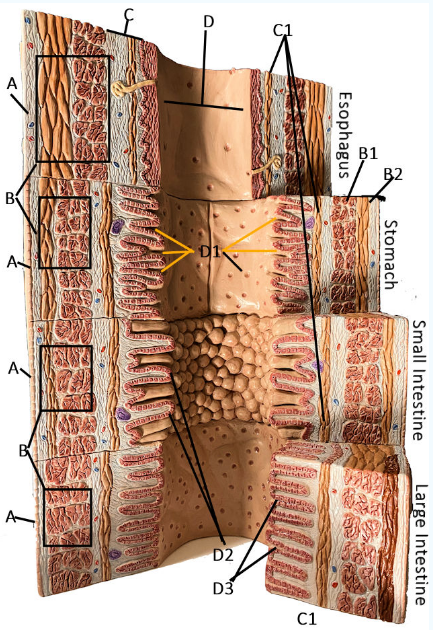

GI Cytology

A

Serosa

B Esophagus

Muscularis externa: skeletal, skeletal/smooth, and smooth, circular and longitudinal

B Stomach

Oblique, circular, and longitudinal smooth muscle

B Small intestine

circular and longitudinal smooth muscle

B large intestine

circular and longitudinal smooth muscle

C

Submucosa: areolar and dense connective tissue

D

Lumen

D1

Gastric glands/pits

D2

Villi of small intestine

D3

Intestinal crypts of large intestine